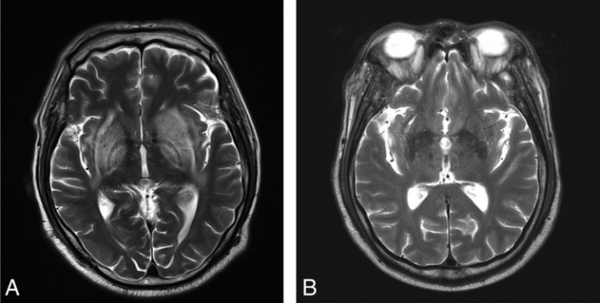

Визуализация мозга чаще всего выявляет его атрофию и увеличение желудочков. Тем не менее иногда, в ограниченном числе случаев при МРТ головного мозга можно обнаружить специфические изменения в области базальных ганглиев, хотя подобные признаки могут сопровождать и метаболический ацидоз, и метаноловую интоксикацию. Изменения, лучше всего заметные в режимах Т2-WI/FLAIR, представляют собой гиперинтенсивные четко очерченные границы скорлупы (латерально — наружная капсула, медиально — внутренняя капсула, внутренняя и наружная мозговые пластинки) с обеих сторон и в целом по форме несколько напоминающие вилку. По сути это является отображением диффузного вазогенного отека базальных ганглиев из-за нарушения процессов ауторегуляции.

На Т2-WI (А) и схеме (В) отображены изменения, имеющие внешнее сходство с вилкой. Яркий гиперинтенсивный ободок очерчивает латеральную (наружная капсула, длинная стрелка) и медиальную (латеральная мозговая пластинка, короткая стрелка и медиальная мозговая пластинка, тонкая стрелка) границы скорлупы с обеих сторон. Бледный шар разделен на 2 части медиальной мозговой пластинкой, которая видна на МРТ при патологических состояниях. FLAIR-изображение (С) иллюстрирует мультифокальные относительно симметричные извилины с высоким сигналом (стрелки) в коре лобной и теменно-затылочной долей, а также в базальных ганглиях билатерально.

На T2-WI изображении (А) определяются типичные «вилкообразные» изменения в базальных ганглиях билатерально. Шесть месяцев спустя на T2-WI изображении (В) видно полное разрешение очагов поражения.